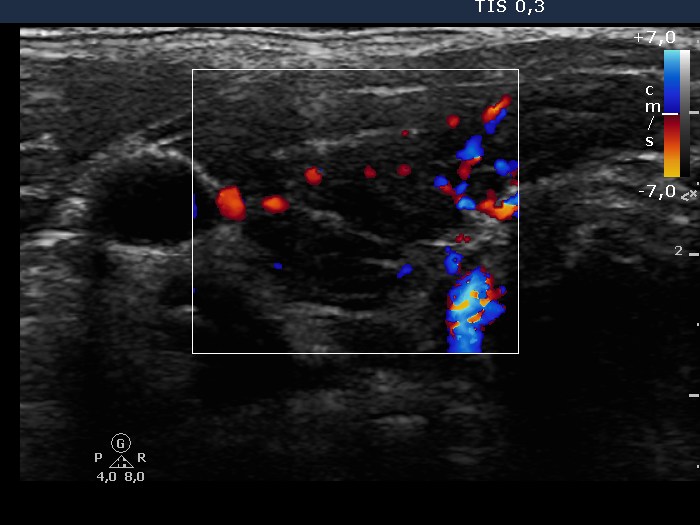

The thyroid gland is located in the neck, just above where your collarbones meet in the middle. Web chronic thyroiditis is caused by a reaction of the immune system against the thyroid gland. The disorder is also called hashimoto disease.

These antibodies cause inflammation in your thyroid gland. This disorder can be either painful or not felt at all. The thyroid gland is located in the neck, just above where your collarbones meet in the middle.

Web chronic thyroiditis is caused by a reaction of the immune system against the thyroid gland. The number of people who have hashimoto’s disease in the united states is unknown. There are four main types of thyroiditis:

Web hashimoto’s thyroiditis, also known as hashimoto’s disease, damages your thyroid function. Web hashimoto’s thyroiditis is also known as chronic lymphocytic thyroiditis or autoimmune thyroiditis. However, the disease is the most common cause of hypothyroidism, which affects about.

This means you develop antibodies [thyroid peroxidase (tpo) and/or thyroglobulin (tg) antibodies] that damage your thyroid gland. The disorder is also called hashimoto disease. The thyroid gland is located in the neck, just above where your collarbones meet in the middle.

This can last for a few weeks or months. Subacute thyroiditis is believed to be triggered by a viral infection. It often results in reduced thyroid function ( hypothyroidism ).